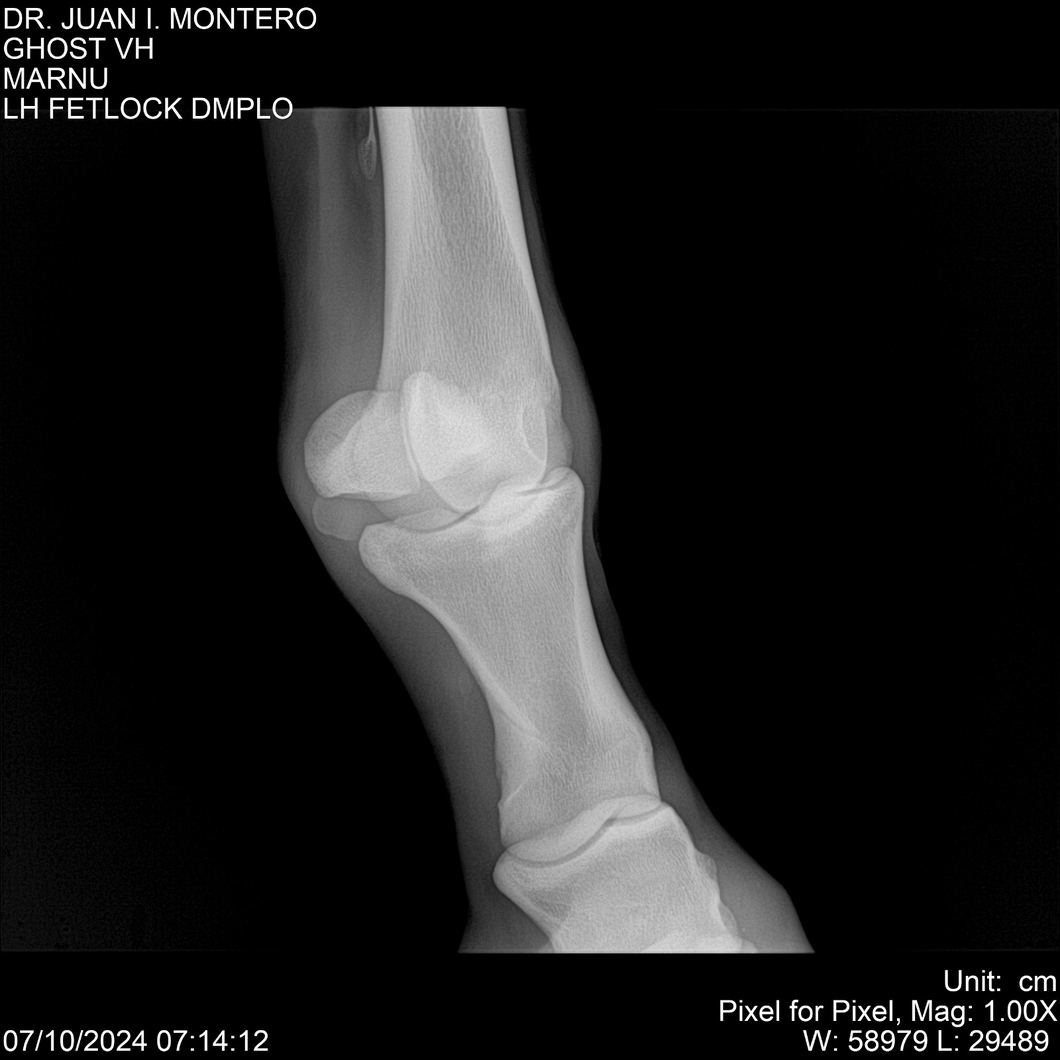

LOTE 15, GHOST VH 🔥 🔥 🔥 Lote Anterior Volver al remate Lote Siguiente Ficha Contacto Montevideo - Ficha del Lote Identificador: #282525 Categoría: Yeguarizos Montevideo - 69 Visualizaciones ClicData Contacto Empresa: Abelenda N. R., Walter Hugo Nombre*: Teléfono* : E-mail* : Mensaje Enviar Registrese gratis Este contenido Exclusivo está disponible sólo para usuarios registrados Ingresar